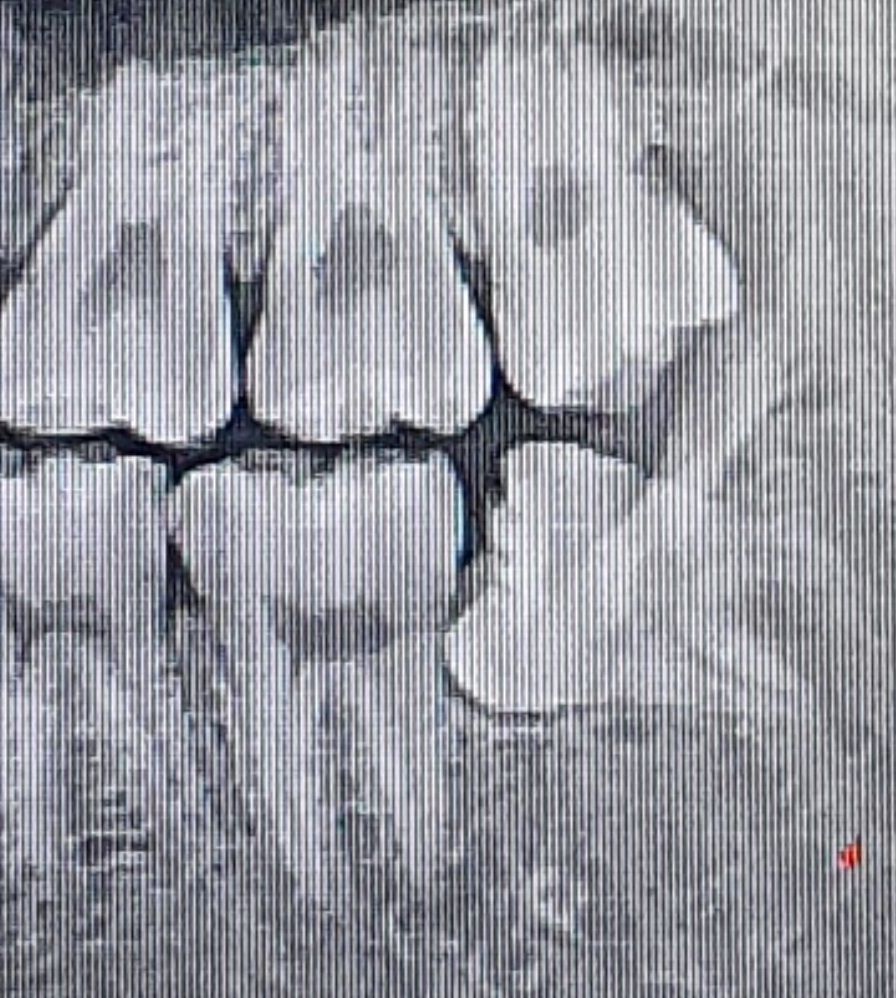

매복 사랑니 발치 후 어금니 패임 전후 사진 다시 올립니다

매복 사랑니 발치 미루다가 뽑았는데 앞 어금니 옆면이 사진처럼 각지고 부자연스럽게 패였습니다

전후 사진인데

• 2번 째 사진

치과의 실수로 해당 모양으로 된 것으로 보이진 않고 치아를 발치 한 후 겹친 모양이 드러난 것으로 보입니다.

• 사랑니가 기울어져 났을 경우에 사랑니가 걸려 있는 부위에 이물질이 남아 있게 되면 충치가 생기게 되고 사진처럼 각진 모양을 보일 수 있습니다 크게 문제가 되지 않기 때문에 걱정하지 않으셔도 되나 불편감이 있다면 해당 부위에 충치를 치료할 수 있습니다 자세한 확인을 위해서 치과에서 진료를 받아 보는 것을 권해 드립니다

• 손상이 일어날 정도로 겹쳐있진 않고 다만 사랑니와 어금니 틈 사이가 관리가 어려웠어서 충치가 생겨있는 것 같습니다 다만 해당부위는 깔끔하게 치료하기는 쉽지 않습니다 오히려 증상이 없다면 지켜보면서 관리를 잘해주는 것이 좋을 수도 있습니다